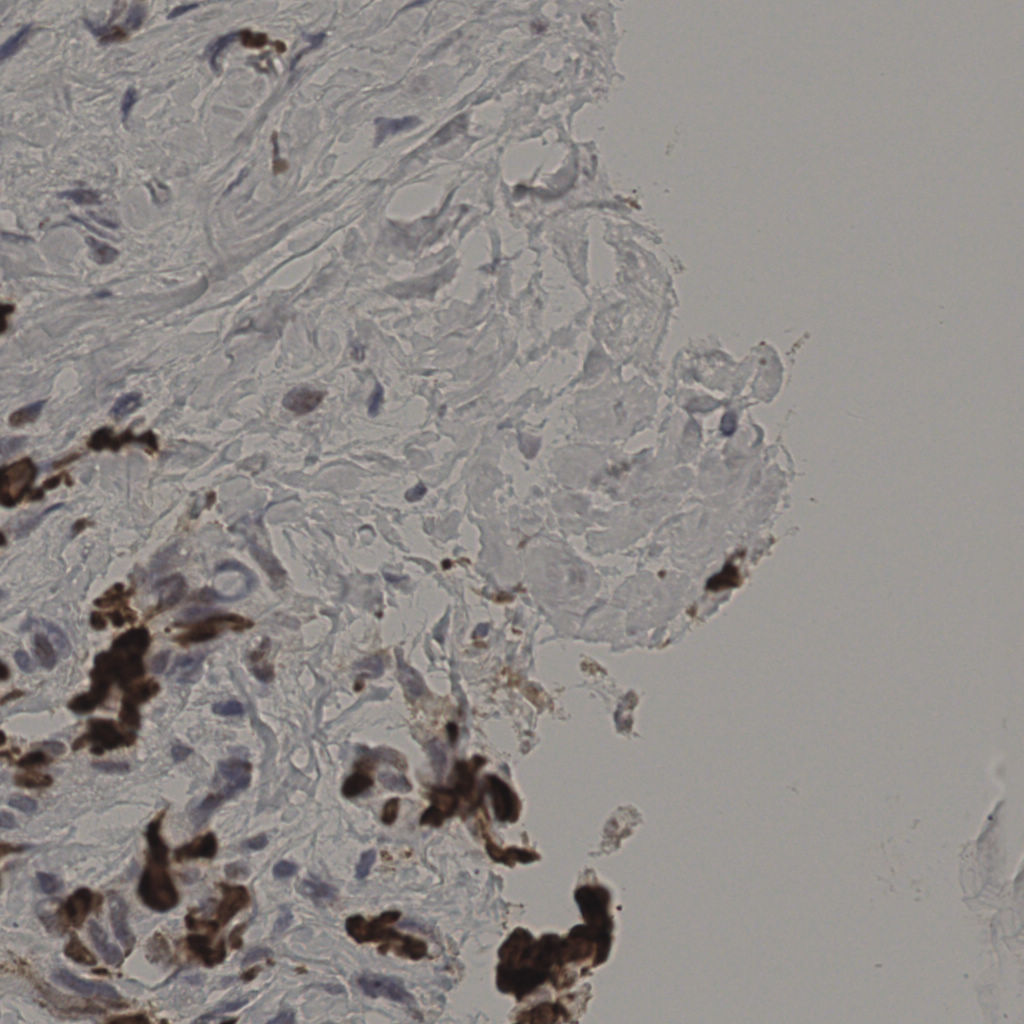

17.75%

Ki67 指数

阴 7986

阳 1723

切片统计

总切片

2640

有效

412

已标记

412

有效率

16%